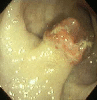

Posted by: Tokyo Pref., 国立癌中心中央病院和九州癌中心共同完成

登记日 1999/01/01

图像 3

X线

内窥镜

病理学分类恶性上皮性肿瘤/腺癌